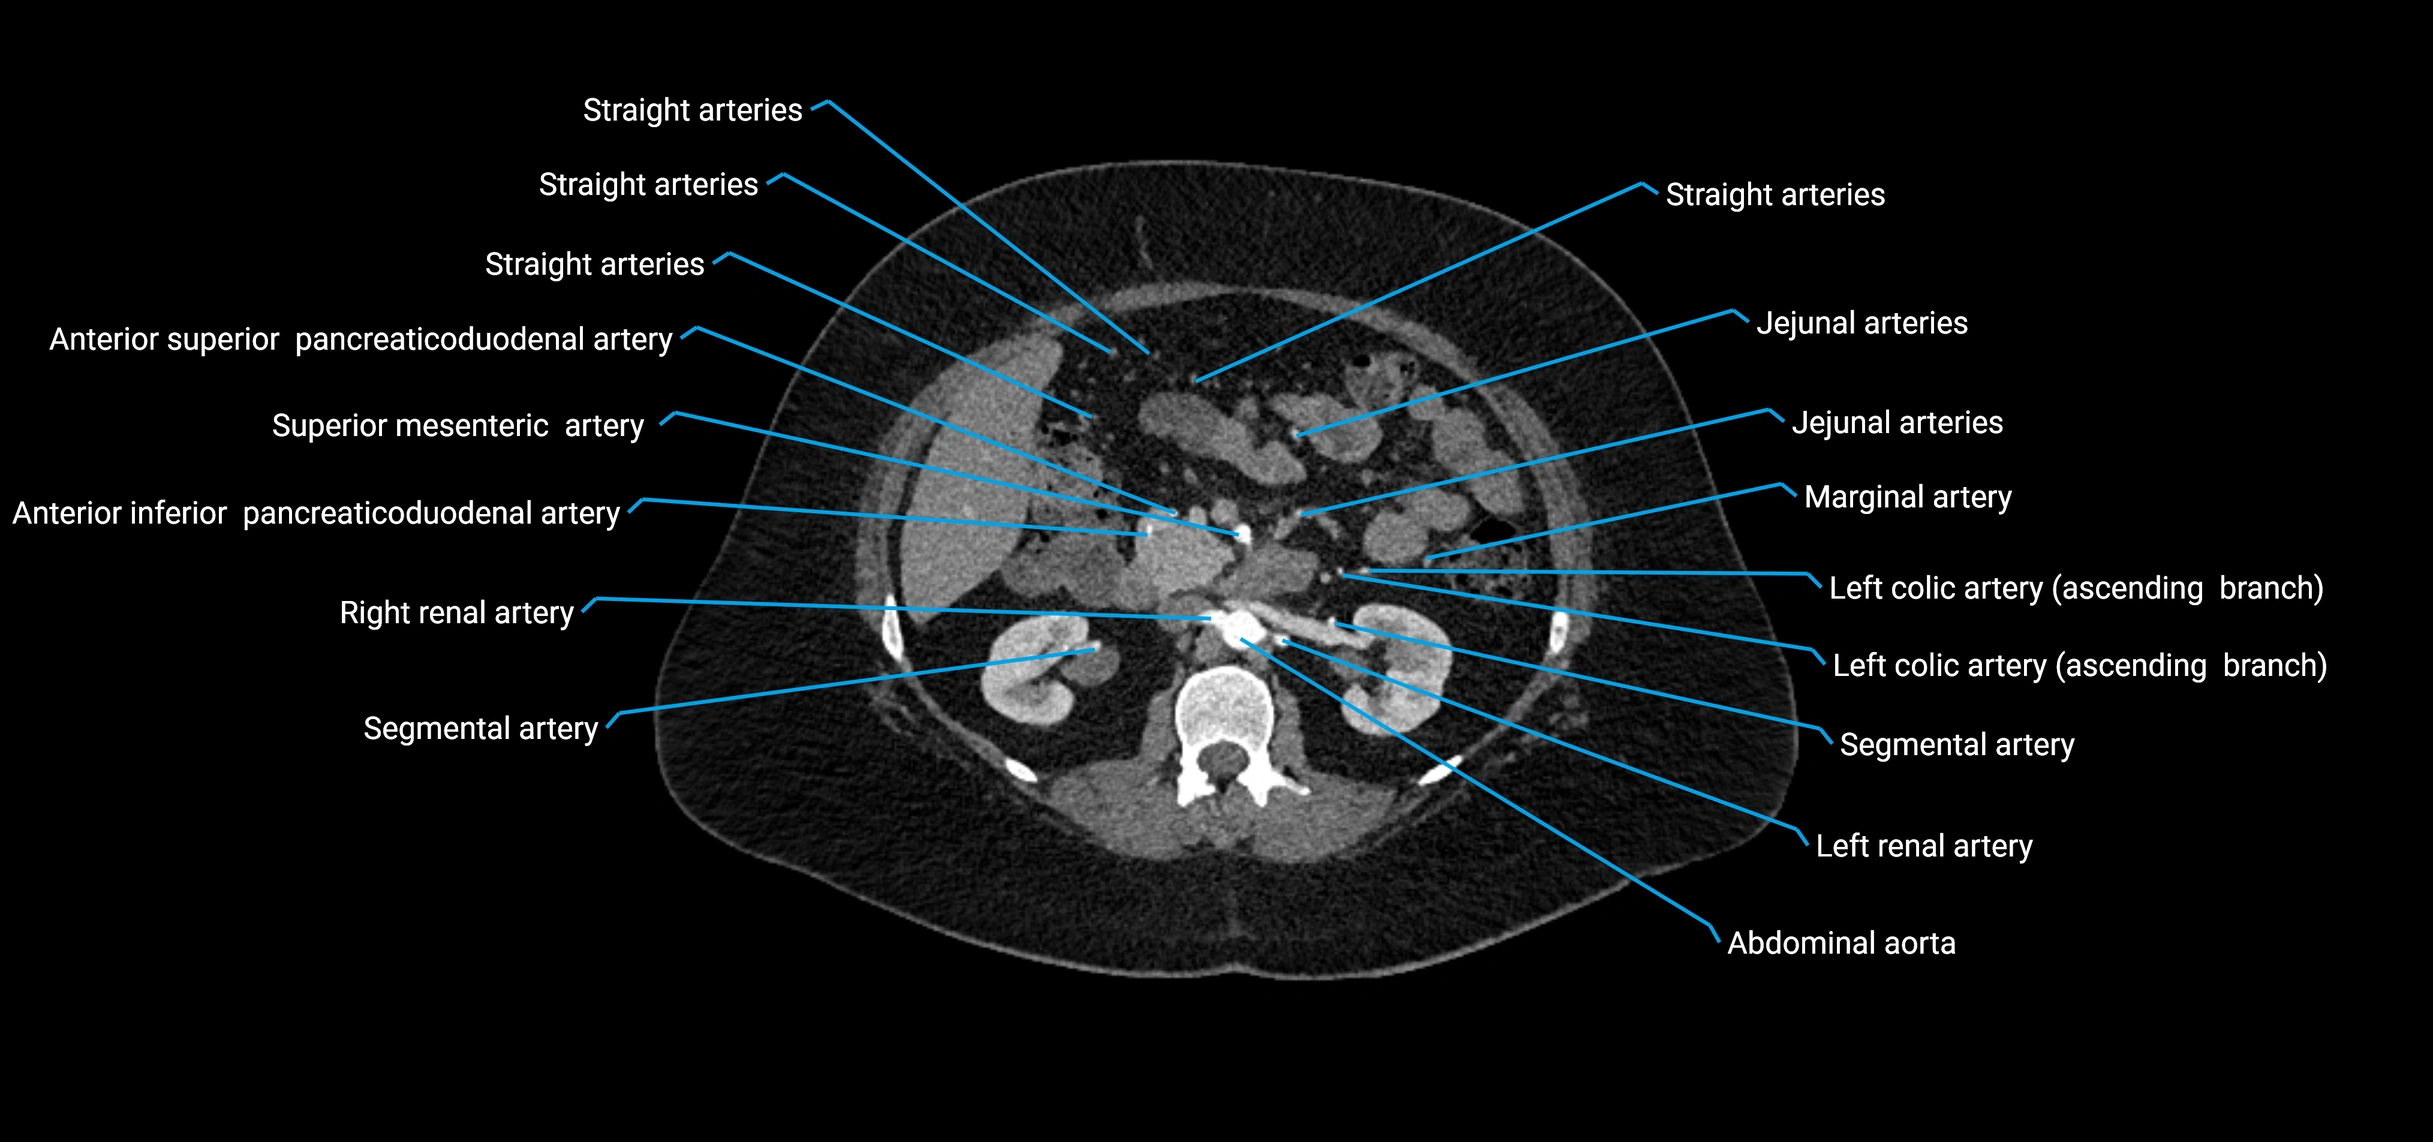

CT images

image